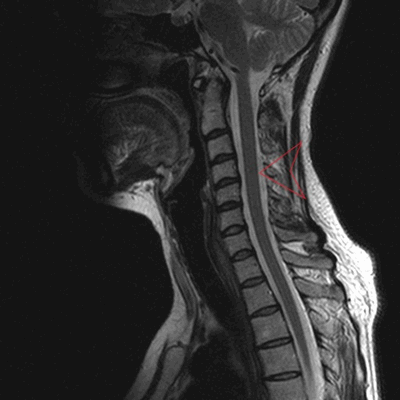

МРТ шеи: оценка спинного мозга (сагиттальная плоскость, Т2 последовательность)

МРТ шейного отдела позвоночника - высокоинформативный неинвазивный способ диагностики, использующий магнитное поле и компьютерную обработку для получения изображений. Преимущества магнитно-резонансного сканирования в сравнении с рентгеновскими методами обследования - отсутствие лучевого воздействия и возможность детализации патологических процессов в мягких тканях: на томограммах видны хрящи, синовии, связки, межпозвонковые диски, спинной мозг, нервы. Если в организме человека нет металлических составляющих или функционирующих устройств с ферромагнитными свойствами, негативные последствия, включая отдаленные, после проведения диагностической процедуры отсутствуют.

МРТ шеи: перелом зубовидного отростка с невральной компрессией (сагиттальная плоскость, Т2 последовательность, STIR)

МРТ позвоночника назначают, если предыдущие способы обследования - КТ, рентгенография, УЗИ с допплером - продемонстрировали неоднозначные результаты или характер выявленных изменений требует уточнения, для оценки индивидуальных анатомических особенностей перед планируемой операцией, в рамках динамического наблюдения за болезнью на фоне лечения. Что показывает МРТ шеи: